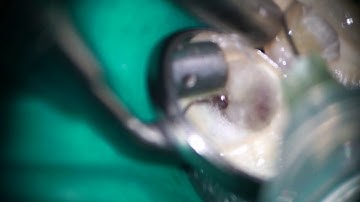

ledge canal bypassed and prepared with TCA technique using HyFlex EDM